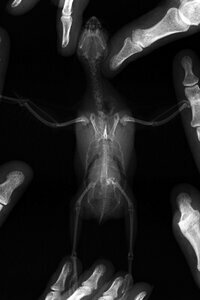

Кстати, и рентген делали из-за этого состояния. Всё-таки выложу его сюда. Сделан 2 месяца назад в начале июня. С того времени она поправилась на 4 грамма.

[​IMG]

Максимальное увеличение (1406 x 2110)

Максимальное увеличение (2072 x 1382)